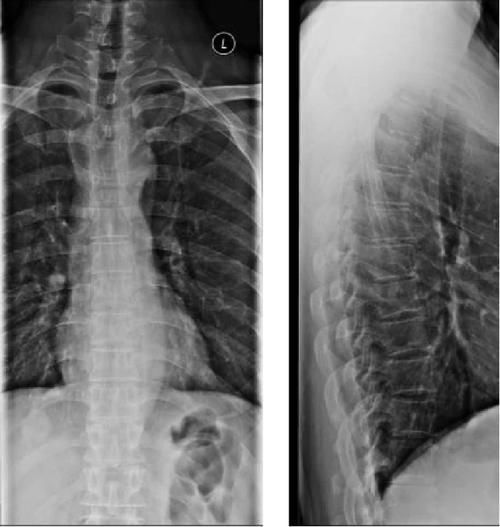

Case15:F,41y;下腰部疼痛7年余,加重1周。

文章插图

Case16:F,35y;阵发性颈部疼痛伴麻木3年,加重伴右上肢继双手麻木。

Case17:F,35y;腰痛数年。